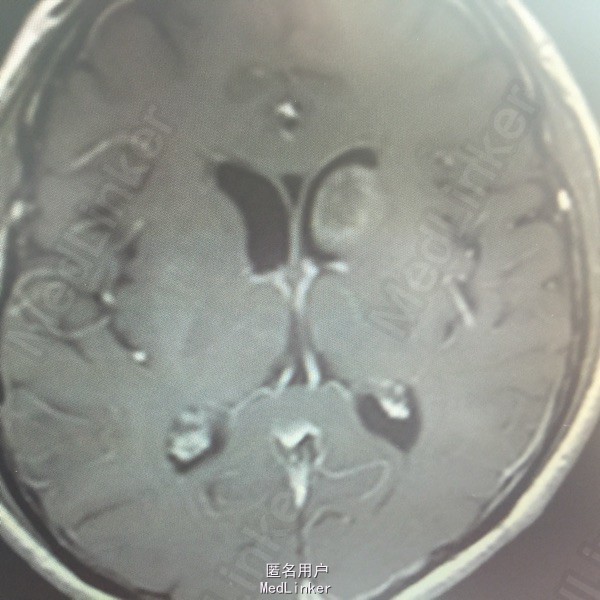

男,54岁,以头痛半个月入院。 现病史:半个月前无诱因头痛,呈胀痛,无呕吐,无意识障碍,病来咳嗽、咳痰,体重减轻约5斤,无发热。 既往史:无特殊。

查体:BP:150/100mmHg,神清语明,两瞳孔等大正圆,直径约3.0mm,光敏,四肢肌力5级,肌张力正常,腱反射艹,左侧共济运动阳性,病理征阳性,脑膜刺激征(-)。 辅查:见下:

肺癌脑转移。 影像解读(影像如何解读是临床工作中非常重要的一环)。 左侧额叶近皮质长Tl长T2信号,局部颅骨缺损,右侧枕叶不规则病灶,TlWl呈中心呈等信号,周围高信号,T2Wl呈高低混杂信号,伴大片水肿,相邻侧脑室后角、胼胝体受压。增强呈不规则环环强化。 已进行局部放疗治疗。